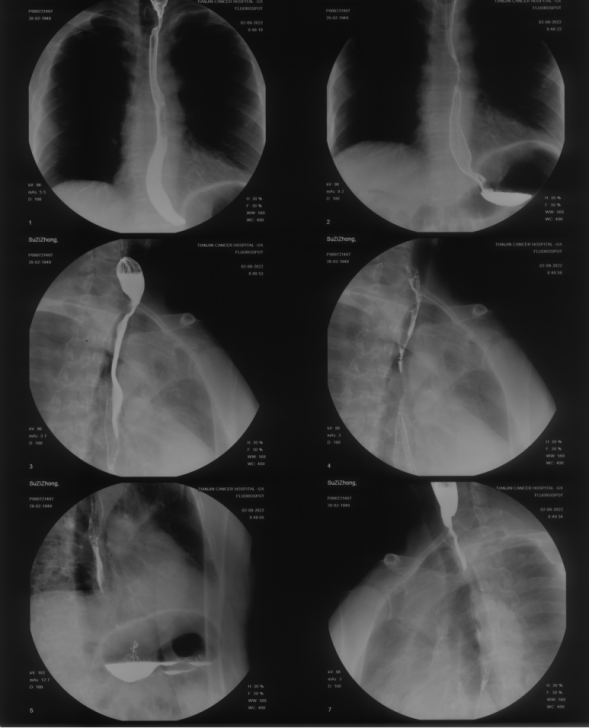

病例二:苏某某,男,73岁,兰州某高校教授。2022 年 6 月 患者出现轻微吞咽困难,因新冠疫情未做进一步检查。2022 年 8 月 16 日患者入住兰州大学第二医院,行上消化道造影显示食管上段偏心性狭窄伴充盈缺损,病变长度约 2.1 厘米。活检确诊食管鳞状细胞癌。2022 年 8 月 30 日,患者入住天津肿瘤医院,行胃镜检查显示食管距门齿约 20 厘米处管腔狭窄。颈部及胸部 CT 显示食管起始部局部管壁增厚,伴右侧颈部淋巴结转移。纵隔内可见多发淋巴结。上消化道造影显示食管上段管腔狭窄,管壁僵硬,黏膜紊乱,充盈缺损约 3.2 厘米。诊断为食管癌 cT2N1M0  Ⅱ期。截止发稿日,重(碳)离子治疗后40个月患者食管肿瘤完全消失,进食顺畅,体力状况良好。

2022年09月2日上消化道造影见食管上段管腔狭窄,管壁僵硬,黏膜紊乱,充盈缺损约3.2cm。

上图为2022年09月10日再次食管镜检查

下图为重(碳)离子治疗后图

为该患者食管上段癌重(碳)离子治疗后40个月,患者食管肿瘤完全消失,进食顺畅,体力状况良好。